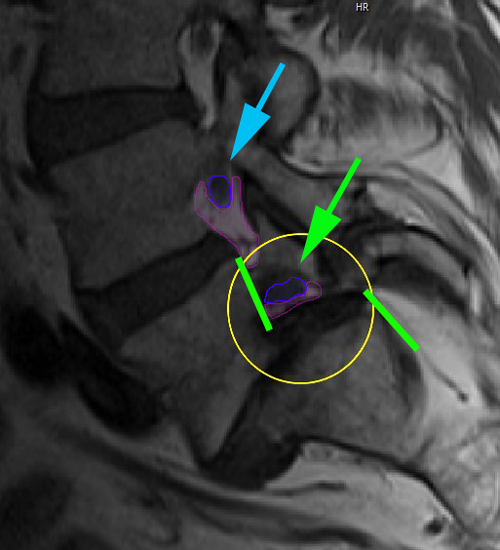

Σπονδυλολίσθηση 3ου βαθμού Ο5-Ι1, ισθμική. Η προσθιολίσθηση του Ο5 σπονδύλου επί του Ι1 απεικονίζεται με την απόσταση ανάμεσα στα οπίσθια τμήματα του σώματος των σπονδύλων (πράσινες γραμμές). Το νευρικό τρήμα παρουσιάζει σημαντική στένωση στο επίπεδο της σπονδυλολίσθησης (κίτρινος κύκλος, τρήμα με φούξια, νεύρο με μπλέ) σε σχέση με το άνωθεν αυτού φυσιολογικό (κυανό βέλος). |